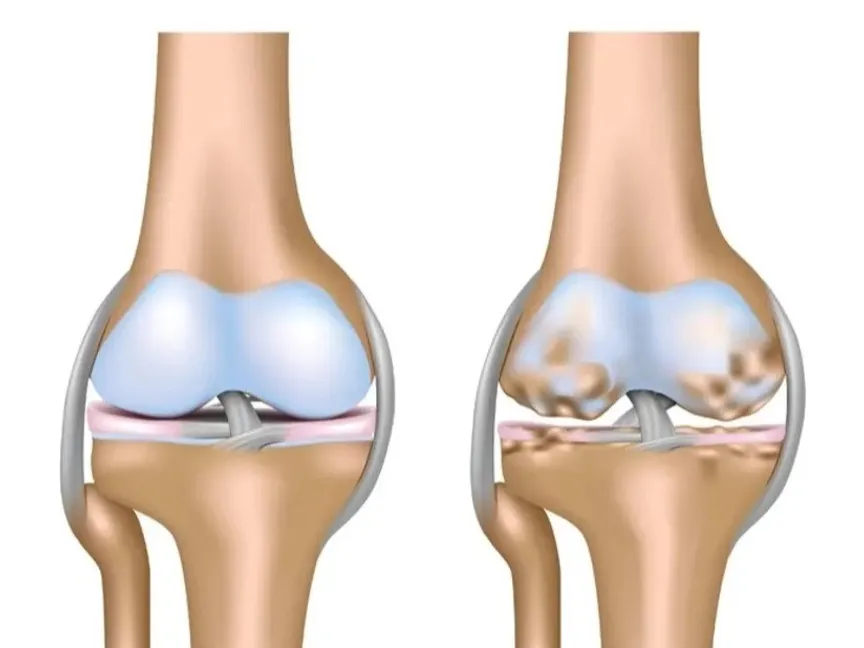

الفصال العظمي

- أكثر أنواع التهاب المفاصل شيوعاً، ويصيب ملايين البشر حول العالم.

- يحدث نتيجة تآكل الغضروف الواقي الموجود عند نهايات العظام مع مرور الوقت.

- يمكن أن يؤثر على أي مفصل، لكنه يظهر غالباً في اليدين، و/ أو الركبتين، و/ أوالوركين، و/ أوالعمود الفقري.

- لا يمكن إصلاح التلف الحاصل في المفاصل، لكن يمكن السيطرة على الأعراض وإبطاء تقدم المرض.

- الأسباب: التلف التدريجي للغضروف ويؤدي لاحقاً إلى احتكاك العظام ببعضها.

- لا يقتصر على الغضروف فقط، بل يؤثر أيضاً على العظام، الأربطة، الأنسجة الضامة، وبطانة المفصل.